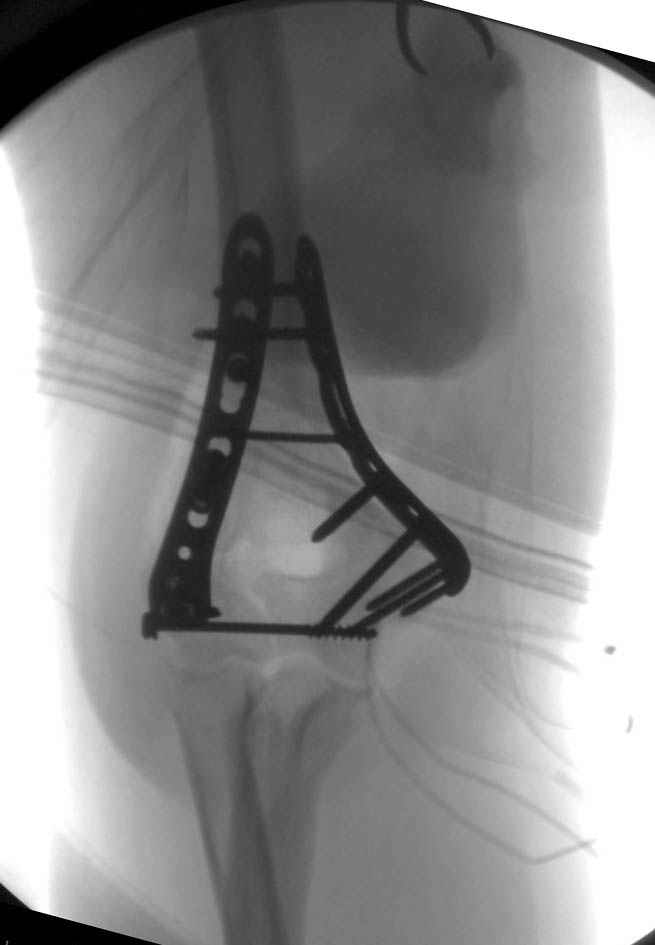

Примерный случай, только перелом был открытый, в задне-медиальной стороне рана около 2 см по характеру "изнутри кнаружи", неврологический статус со слабостью сгибания мизинца, также слабая абдукция и аддукция указательного пальца и сгибания в кисти.

Больному сделали обработку и наложили временный аппарат внешной фиксации плечо-предплечье.

На шестой день сделали открытую репозицию чрезлоктевым доступом двумя locking plate, локтевой нерв был ушибленным, после операции положительная динамика в Flexor Carpi Ulnaris. Фиксацию локтевого отростка произвели tension band technique с дополнительным шурупом.

Этапы операции на снимках....

Джолдас Кульджанов

Djoldas Kuldjanov, MD

Department of Orthopedic Surgery

St. Louis University Medical Center